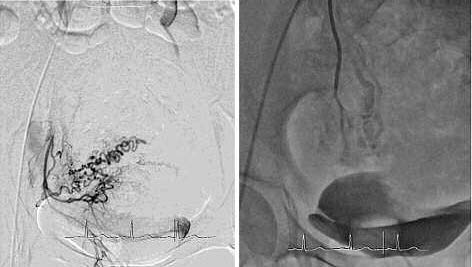

Через катетеры, установленные последовательно в левой и правой маточной артерии, введены сферы эмболизата Contour (Boston Scientific): 1 флакон 500–700 мкр дробно. На контрольных ангиограммах: афферентные артерии к образованиям матки окклюзированы. Длительный стаз контрастированной крови в стволах левой (рис. 2, б) и правой (рис. 3, б) маточных артерий. Катетер и интрадьюсер удалены. Наложена асептическая давящая повязка. Нежелательных реакций и осложнений интраоперационно не наблюдалось.

Рис. 3. Процедура ЭМА. Ангиограмма правой маточной артерии до введения (а) и после введения эмболизата (б).